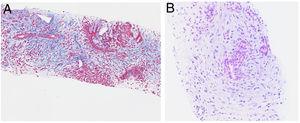

Malacoplaquia apendicular como raro diagnóstico diferencial de mucocele. A propósito de un caso

Francisco José Almoguera González, Cristóbal Muñoz Casares, Carlos González de Pedro, Lourdes Galán Villamor, Francisco Javier Padillo Ruiz

Cir Esp. 2024;102:174